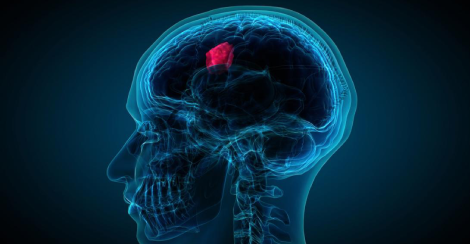

Dr. Kanishk Goyal

NeurosurgeryM.B.B.S, Ms, Mch (Neurosurgery)